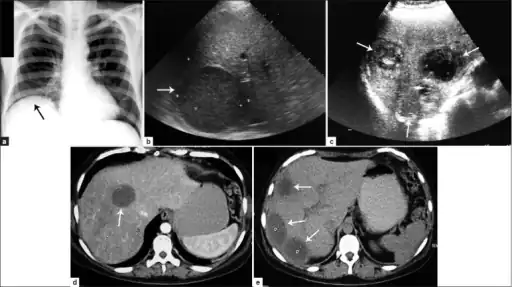

a) Amoebic liver abscess showing the elevation of the right hemi-diaphragm b)single large amoebic abscess and c) three amoebic hepatic abscesses. d) Contrasted computed tomography (CT) scan of a single abscess and e) three clear amoebic liver abscesses

a) Amoebic liver abscess showing the elevation of the right hemi-diaphragm b)single large amoebic abscess and c) three amoebic hepatic abscesses. d) Contrasted computed tomography (CT) scan of a single abscess and e) three clear amoebic liver abscesses -